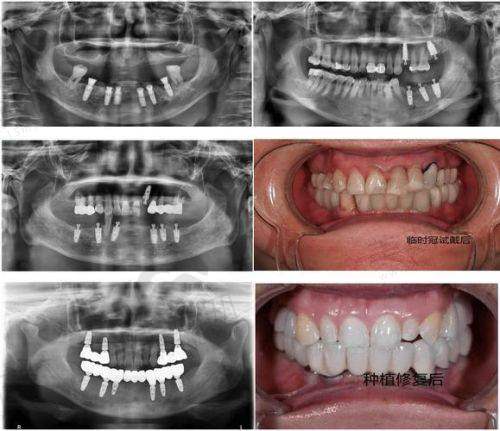

在技术方面,该医院采用高超的微创、即刻种植牙技术。这种技术在种植过程中对周围牙齿和组织的损伤比较小,大大减轻了患者的痛苦。而且医生操作技术熟练,他们都经过专门培训,在种植牙领域有多年实践经验,能够为患者提供专精的治疗。

其技术亮点在于有一套完善的种植前评估体系。通过详细的口腔检查、CT扫描等手段,能够正确判断患者是否适合种植牙,以及确定种植位置,这有助于提高种植牙的成功几率。

不同的乐清牙科医院在技术上各有特色。乐清齿逸口腔采用高超的微创、即刻种植牙技术,减少了对周围牙齿和组织的损伤,患者术后修复快。乐清牙世佳口腔的种植前评估体系完善,通过详细检查和CT扫描正确判断患者情况,提高了种植牙的成功几率。